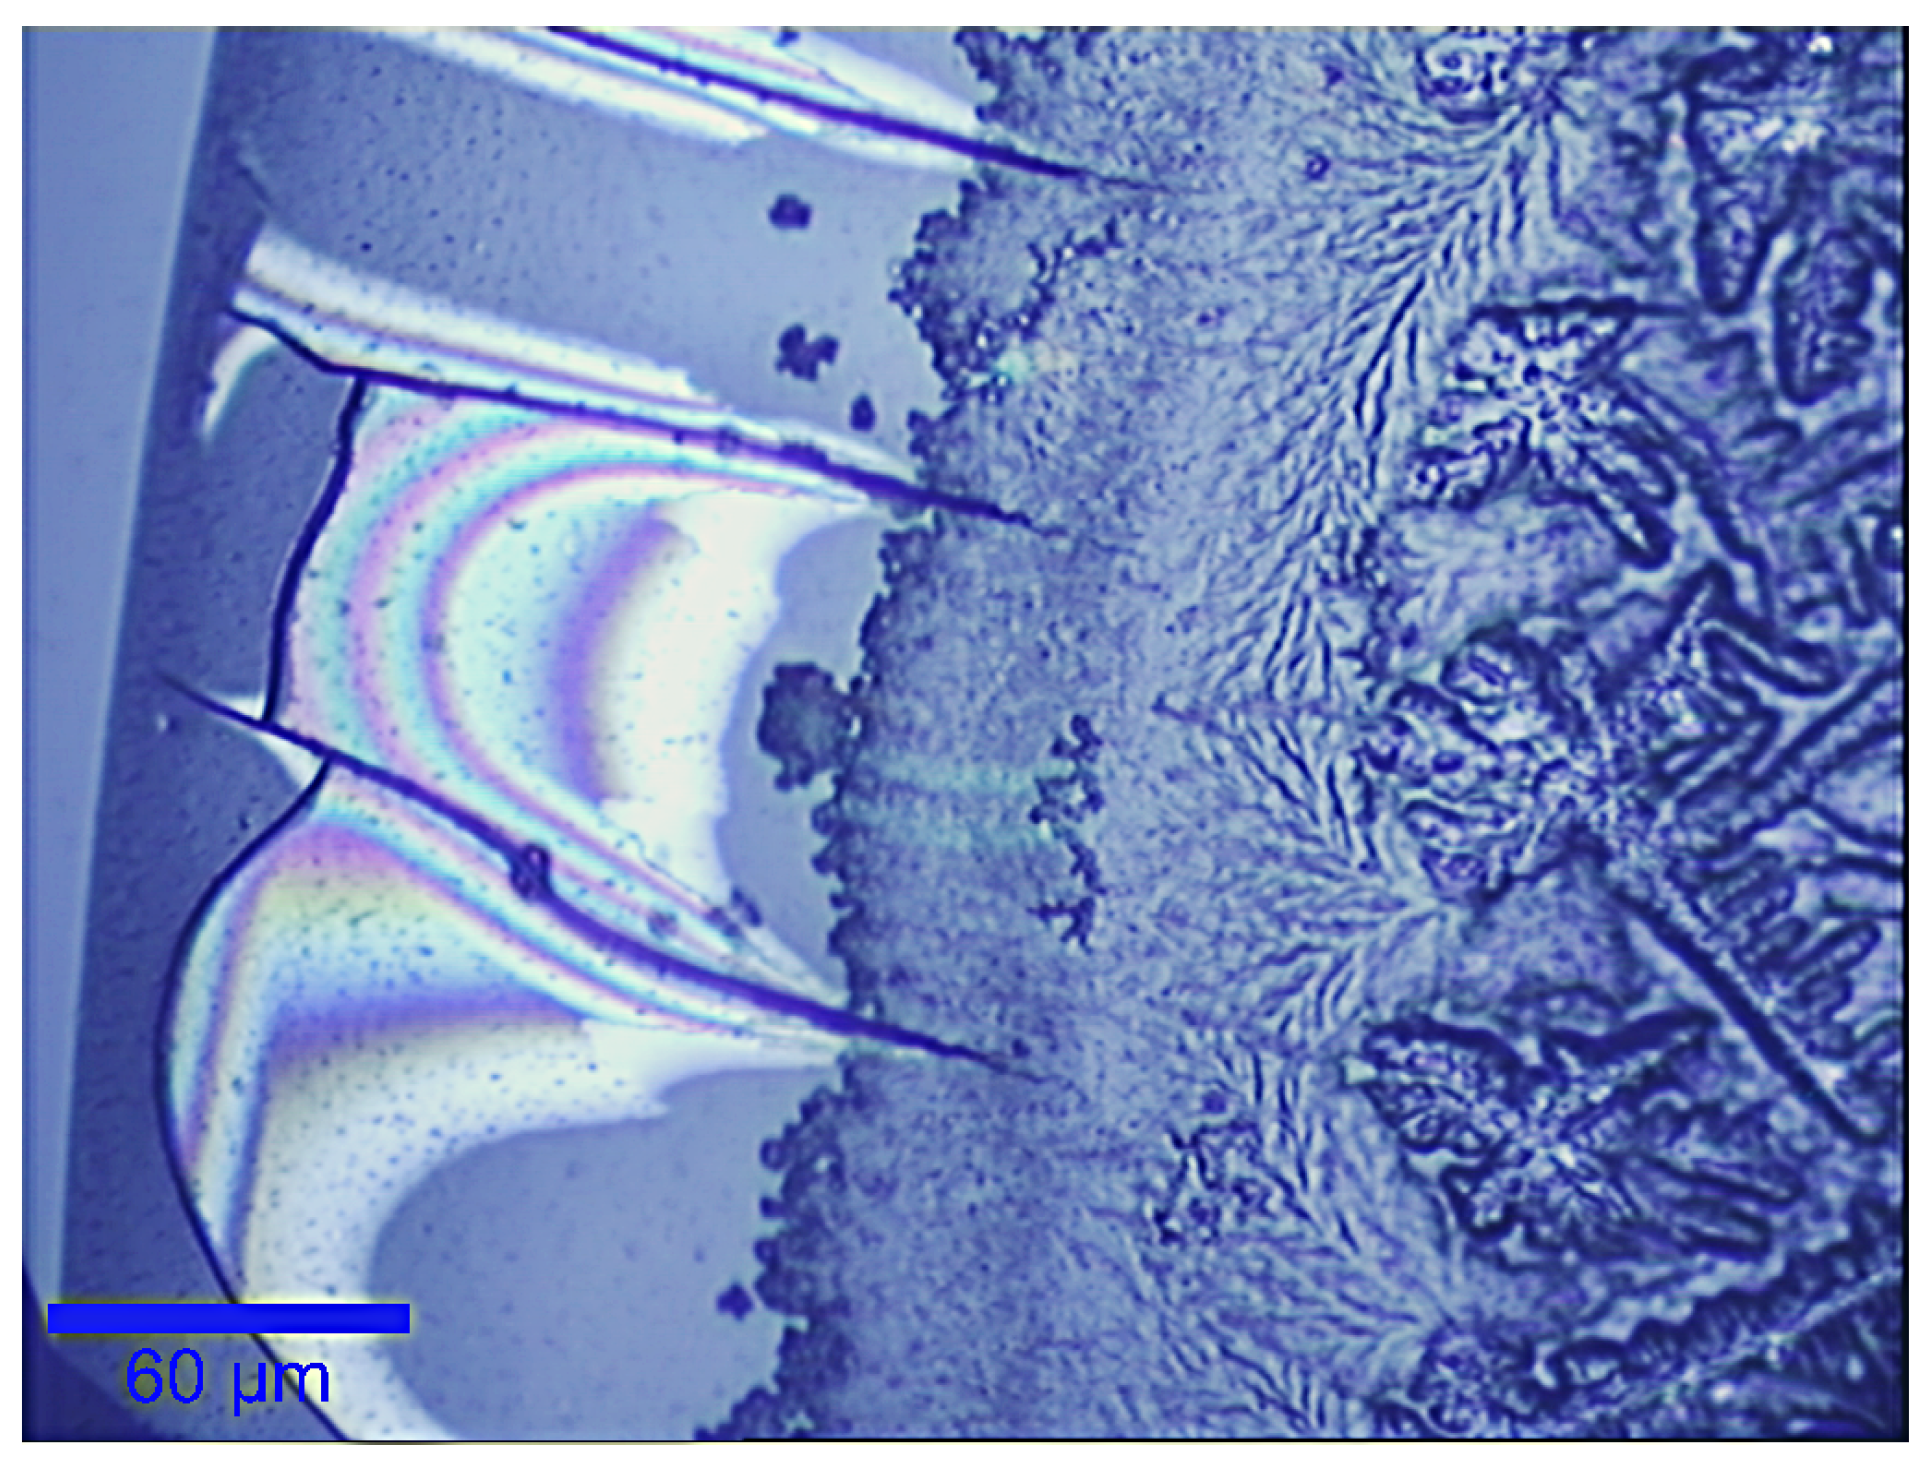

- Filik, J.; Stone, N. Raman point mapping of tear ferning patterns. Proc. SPIE 2008, 6853, 685309. [Google Scholar] [CrossRef]

- Golding, T.; Brennan, N. The basis of tear ferning. Clin. Exp. Optom. 1989, 72, 102–112. [Google Scholar] [CrossRef]

- Murube, J. Tear Crystallization Test: Two Centuries of History. Ocul. Surf. 2004, 2, 7–9. [Google Scholar] [CrossRef]

- Pearce, E.; Tomlinson, A. Spatial location studies on the chemical composition of human tear ferns. Ophthal. Physiol. Opt. 2000, 20, 306–313. [Google Scholar] [CrossRef]